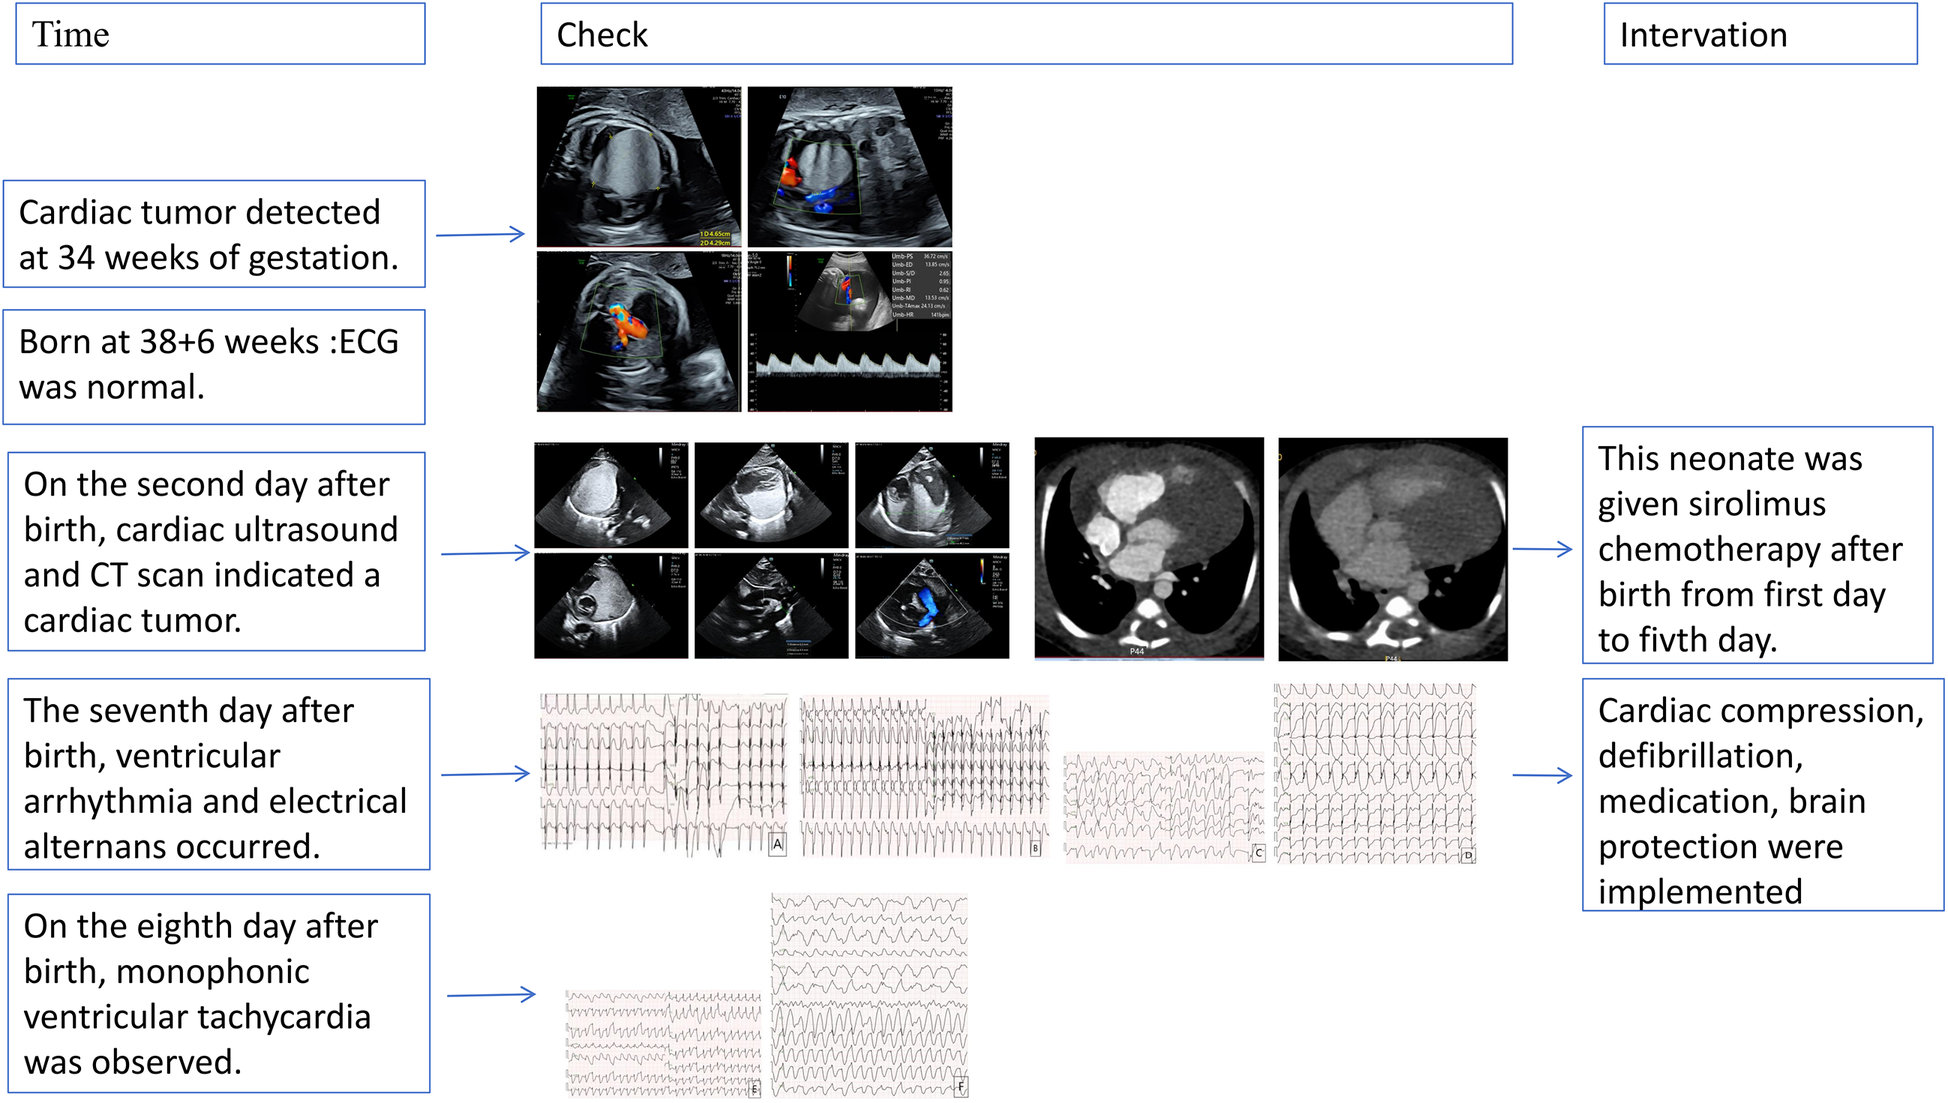

This case illustrates the difficulties in treating neonatal ventricular tachycardia induced by a cardiac tumor, which caused severe arrhythmias unresponsive to pharmacologic and electrical treatments. Figure 3 shows the ECG results of the child measured from birth to the 8th day after birth. Although rare, neonatal cardiac tumors can significantly disrupt cardiac function and rhythm (6–8). The timeline for the case's examinations and interventions is shown in the Figure 4.

Figure 4

The timeline for the case's examinations and interventions.